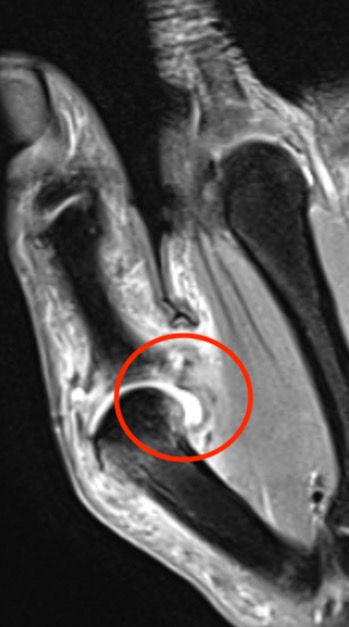

X-ray

Bony avulsion

1. Small fragment pulled away from proximal phalanx

2. Large intra-articular fracture involving >1/4 articular surface

3. Salter Harris III in pediatric population